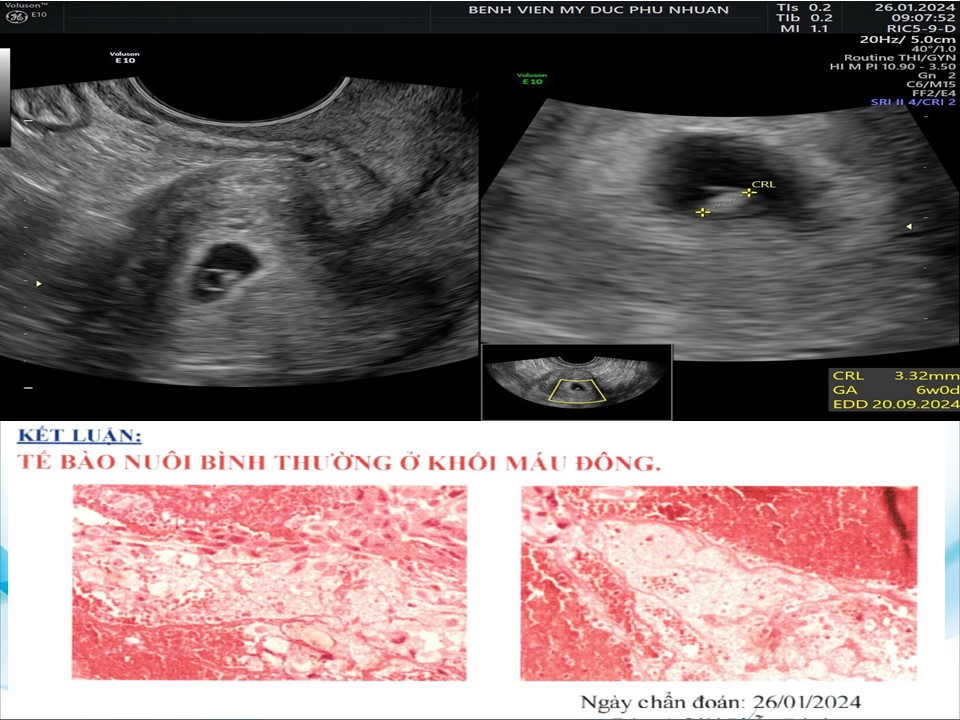

Siêu âm đánh giá khả năng sống của thai giai đoạn sớm

BS. CKI Phạm Thị Phương Anh - BV Mỹ Đức